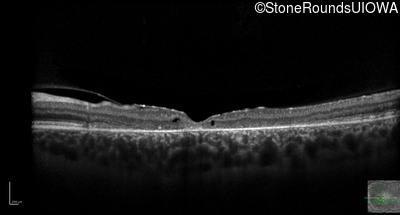

Optical Coherence Tomography - Left - 10/125 -1

Exemplar / OCT Stack